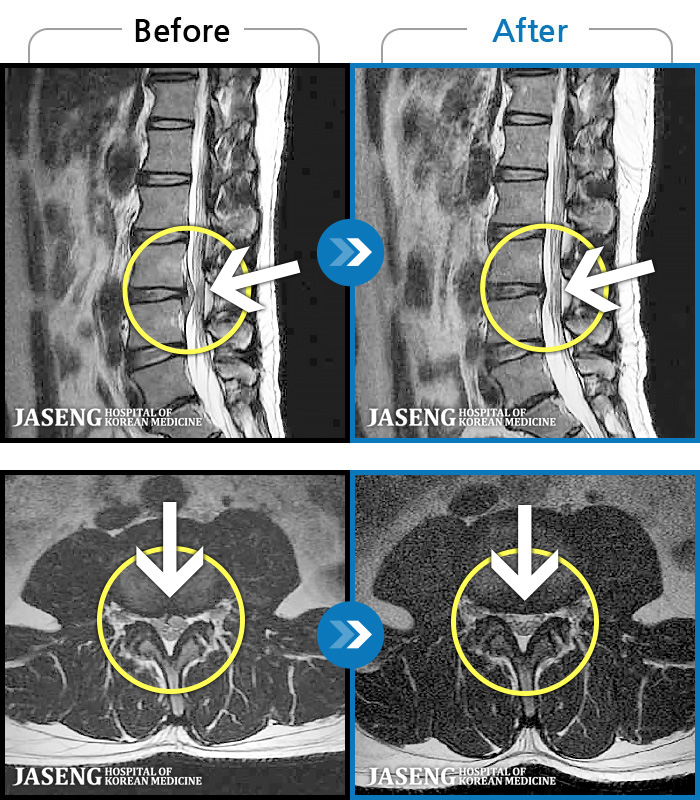

MRI ġ

1,240 MRI ũ ʸ Ȯϼ.

[_㸮ũ] 㸮 ϰ , ̾ ϼ̽ϴ.

[ϻ_㸮ũ] ϰ ӵǾϴ. ߰ Ͽ ߰ Ǵ ߵ ̻ ȣϴ ¿ϴ.

[λ_㸮ũ] 㸮 㸮 ̸ ִ.

[Ȼ_㸮ũ] 㸮 ְ ٸ ȱⰡ .

[_㸮ũ] 㸮 , ٸ ̾ ϼ̽ϴ.

[õ_㸮ũ] ߲ 㸮 , ٷ

[ϻ_㸮ũ] ݺ ӵǸ ڼ ÿ ȭǴ ߵ ̻ ȣϴ ¿ϴ.

[ϻ_㸮ũ] ؽϰ ߰ ̴ · ϻȰ ¿ϴ.

[ؿ_㸮ũ] 㸮 ϰ